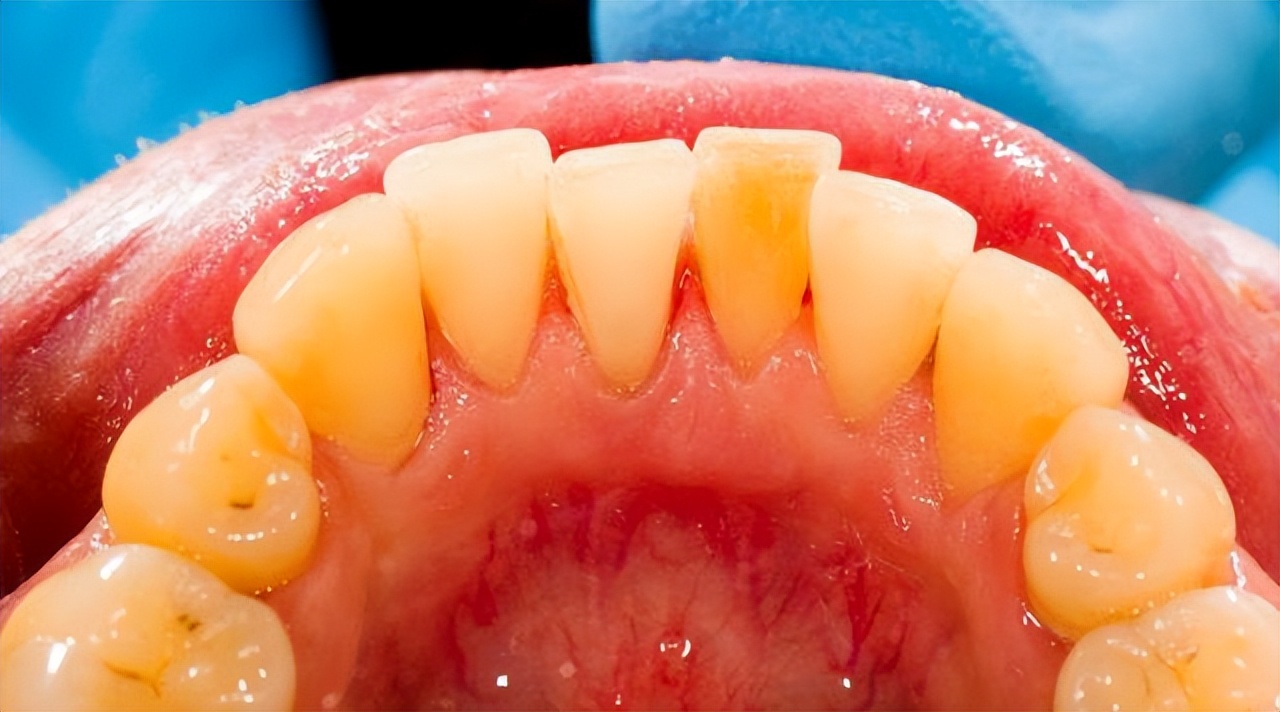

牙结石附着在牙冠或者牙齿的颈部,主要是由食物残渣物,口腔上皮细胞和唾液中的矿物质脱落和脱落形成的钙化矿物质形成。

牙结石颜色是白色或者黄色,如果吸烟会慢慢变成黑色,主要分为上牙龈结构和龈下结石。

我们每天坚持刷牙,对于清除牙结石有一定效果,牙结石刚开始形成时颜色为浅黄色,质地比较软,此时选择正确刷牙方法和正确清洁用品能够消除。